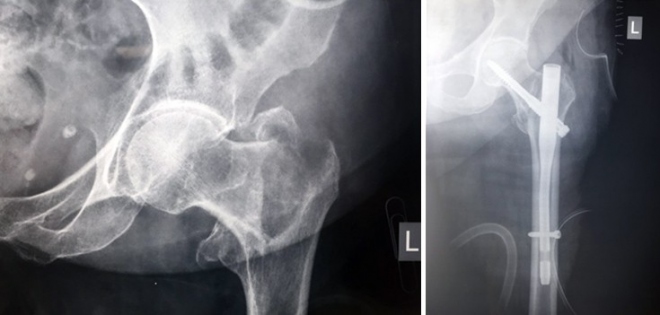

Τα κατάγματα του ισχίου ανάλογα με το σημείο του οστού που συμβαίνουν χωρίζονται αδρά σε διατροχαντήρια και υποκεφαλικά.

Για τα διατροχαντήρια κάταγματα, η σύγχρονη ελάχιστα επεμβατική χειρουργική θεραπεία είναι τα ενδομυελικά συστήματα -Gamma nails (αυξημένη σταθερότητα). Και εδώ, λόγω του ότι η ήλωση γίνεται κλειστά, έχουμε μικρό χειρουργικό χρόνο, μικρές απώλειες αίματος και χαμηλή νοσηρότητα (μειωμένος κίνδυνος λοίμωξης).

Μετεγχειρητικά πετυχαίνεται η άμεση έγερση απ’ το κρεβάτι, η άμεση βάδιση και η αποφυγή των επιπλοκών που δημιουργούνται από την παρατεταμένη κατάκλιση.